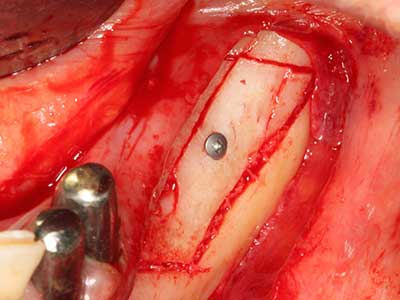

Пиезохирургията има допълнителни предимства при събиране на костни блокове. В допълнение към високата прецизност при остеотомията, описана по-горе, употребата на фините режещи накрайници значително намаляват загубата на материал. Голяма загуба на материал по време на събиране може да се очаква с дебелите накрайници, особено при употреба на борери Линдеман (Lakshmiganthan, Gokulanathan et al. 2012). Базалното разделяне, което е необходимо, особено за присадка на блок при ретромолар, е улеснено от специално създадени правоъгълни триони. В резултат на това, пиезохирургията е разглеждана като прецизна, улеснена и безопасна процедура за събиране на костни блокове в ретромоларното пространство (Happe 2007) (Фиг. 1-12).

Костната тъкан е не само минерализирана структура, тя съдържа и съществено количество колагенови влакна. Това означава, че тя има не само добра компресивна сила, но и известна степен на гъвкавост, която може да се възприеме като предимство при извършване на костна аугментация. В класическата процедура по разширяване чрез костно разделяне, атрофиралият алвеоларен гребен е разделен надлъжно и внимателно разширен след достигане на подходящата остеотомна дълбочина (Фиг. 13-16), в идеалния случай без допълнително отстраняване на периостеума (Brugnami, Caiazzo et al. 2014, Stricker, Fleiner et al. 2014). Системите с винт и пластини с увеличаване на разстоянието при разширяване са доказали ефективността си при разделяне на двете костни ламели, оставайки под прага на фрактурите. В общи линии, оставащата ширина на костта от поне 3–4 mm е задължителна (Chiapasco, Zaniboni et al. 2006), за да се гарантира добра гъвкавост и достатъчно костно покритие за бъдещото поставяне на импланти. Ако е необходимо, вертикалната остеотомия на едната или двете страни може да подобри гъвкавостта. Комбинацията с допълнителни техники за аугментация, особено в букалната страна, е описана като алтернатива на класическата техника.